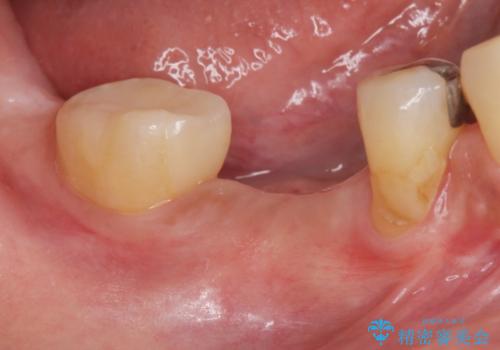

- 歯茎が腫れて痛いとの事で来院。

保存できない状態でしたので抜歯をして歯槽堤保存術を行いました。その後大臼歯部にインプラント治療を行いました。